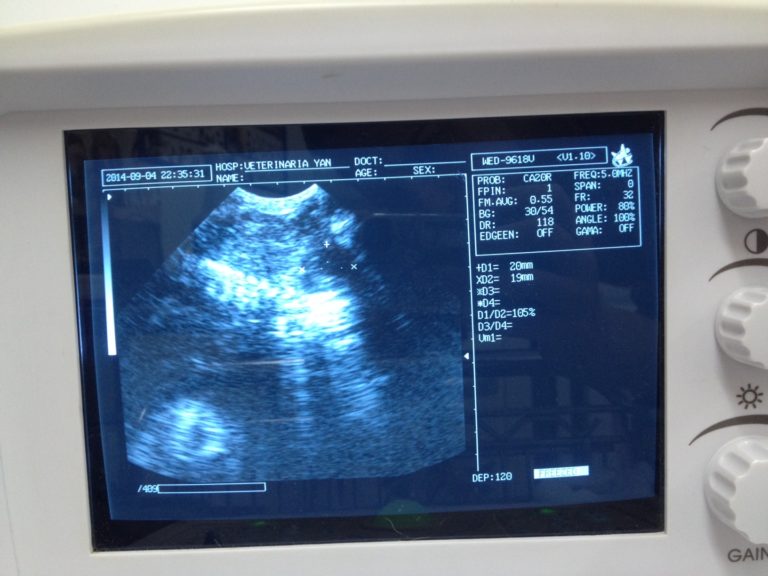

We arrived at Veterinarian Yesse Alpizar, in Herradura. I’ve taken other patients to Yesse before. She is one of the kindest and smartest vets I’ve met and she also happens to have a clinic equipped with a digital X-ray and ultrasound machine. After getting a complete history on momma sloth, Yesse examined her and agreed with me that she was in labor. We first took an X-ray. It was amazing to see the little life inside of mom’s belly…but unfortunately the baby was in a breech position and mom was completely full of urine and feces (sloths can hold up to 30% of their body weight in urine/feces) meaning that the baby changing position wasn’t likely. At this point, c-section was discussed but we needed to check the baby with an ultrasound to confirm a heartbeat and the exact position. With the first swipe of the ultrasound probe, we didn’t see a heartbeat. My heart sank. Just one day before I had felt the baby move inside of mom’s belly. So I knew that recently it was alive and I could only hope that it still was. Yesse kept swiping the probe around mom’s belly searching and searching for a tiny flicker of the heart. Was the baby still alive?!?